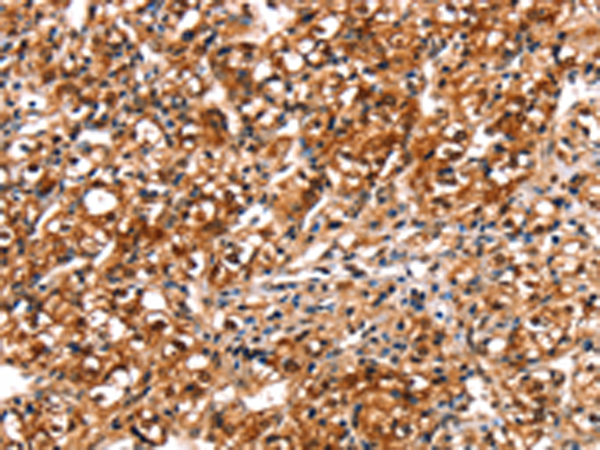

分类: 科研抗体货号: P08718别名: MRB; AOVD3; ECSM4应用: IHC反应种属: Human